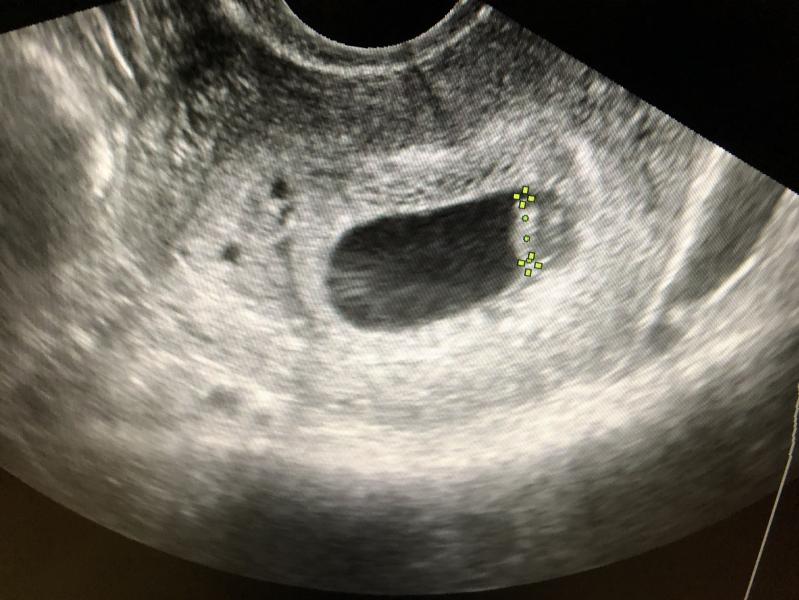

Доброго времени суток. Девчат хотела уточнить было ли у кого-нибудь , что первое узи выглядело так, а потом сказали , что беременность многоплодная и будет двойня?

Да, все может быть